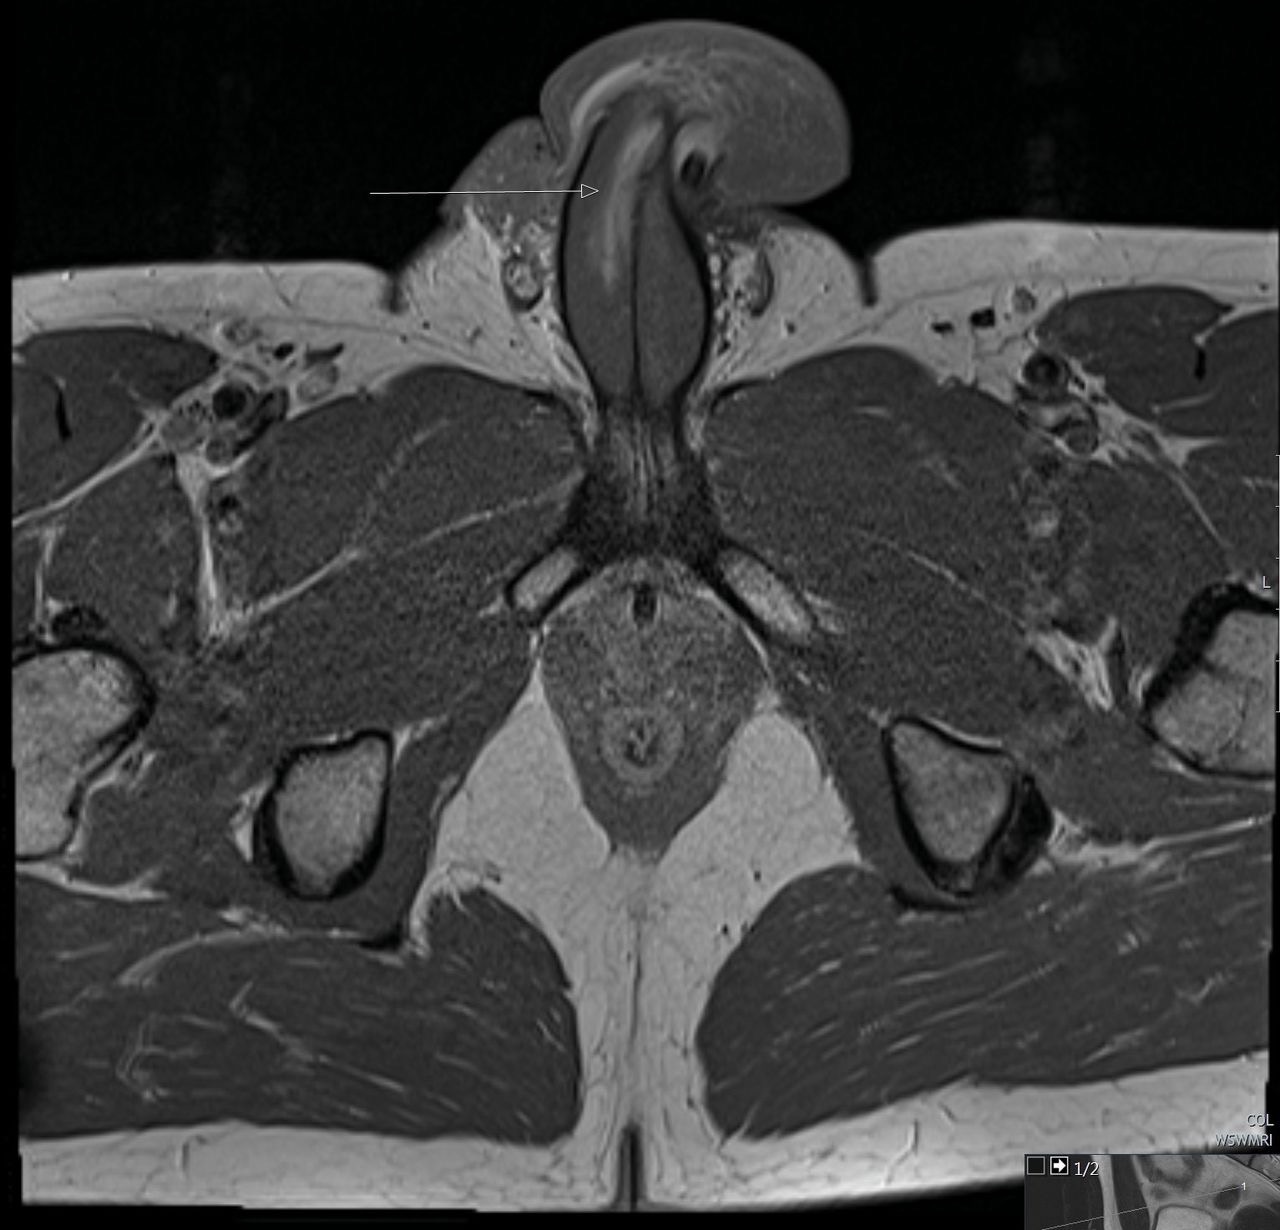

МРТ полового члена

Демонстрация гематомы, которая примыкает к дистальному концу правому кавернозному корпусу.